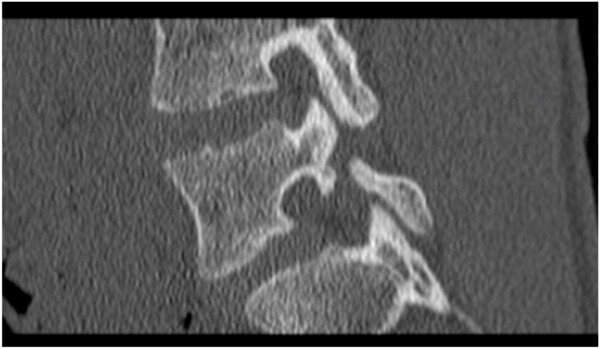

척추관협착증

척추관협착증은 중년 이후에 흔하게 나타나는 병으로, 여러 가지 원인에 의해 목에서 허리까지 신경이 지나가는 관이 뼈나 관절에 의해 척추관이 좁아져서 신경이 눌리게 되는 증상이다. 대부분 선천적 원인도 있지만, 40대 이후에는 노화 현상에 의한 퇴행성이 원인이다.

척추전방전위증

척추 뒷부분에서 위쪽과 아래쪽의 뼈를 고정하는 고리처럼 생긴 관절돌기가 손상을 입거나 관절의 퇴행성 변화 등으로 인해 척추뼈가 어긋나서, 척추뼈가 정상적인 정렬을 이루지 못하고 앞으로 빠져 있는 상태에서 척수 신경이 눌려 통증을 일으키게 되는 질병이다. 대개 40세 이후의 여성에게서 5배 정도 많이 발병되는 질환이며, 제4번 요추에서 발병빈도가 가장 높다.

척추분리증

척추분리증은 척추뼈 앞쪽과 뒤쪽 구조물의 연결고리가 끊어지며 분리되는 질환이다. 초기에는 요통이 별로 없지만, 추간판의 퇴행성 변화가 시작되면 분리된 척추뼈가 앞으로 밀리게 되어 전방위증으로 악화할 수 있으므로 조기검진을 통해 빨리 치료를 받아야 한다.